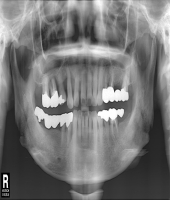

| ● 진료과목 : [임플란트] 틀니 사용중, 임플란트로 교체하기

| ● 내용 : 하악틀니 사용 중 불편감으로 임플란트로 교체한 예 |